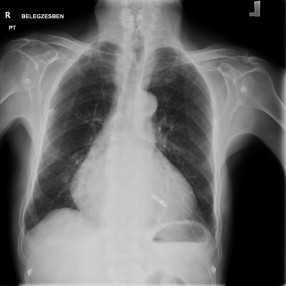

A Micra™ pacemaker mérete kevesebb mint egy tizede a hagyományos pacemakerekhez képest. Az eszköz teljes egészében a szívbe kerül beültetésre kiegészitő elektróda nélkül, így közvetlenül tudja segíteni annak szabályos működését. A készülék behelyezését röntgen átvilágítás alatt végzik, a beteg lágyéki vénáján keresztül bevezetett katéter segítségével. A megfelelő hely elérését követően a felvezető katéter eltávolításra kerül, és a 2 gramm tömegű szívritmushenger pedig a helyén marad.